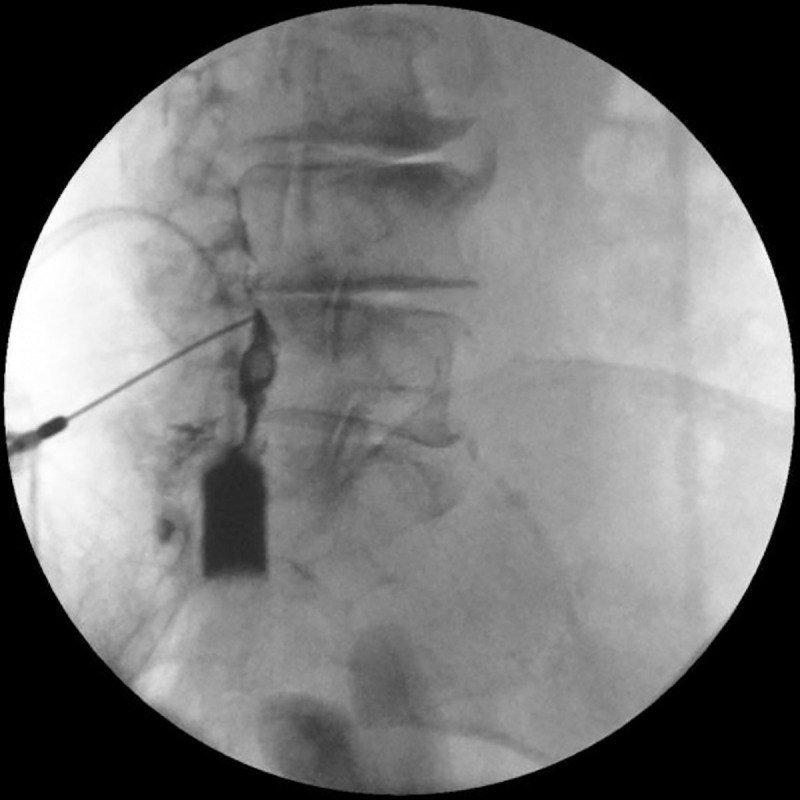

AP (A) and lateral (B) fluoroscopic views during interlaminar epidural steroid injection showing contrast localized to the epidural space.

8. Contrast injection: 1-2 mL of non-ionic contrast under real-time fluoroscopy to confirm epidural spread pattern in at least two planes (AP plus CLO or lateral)

5. Fluoroscopic confirmation: Lateral view to confirm the needle is within the sacral canal — not subcutaneous or presacral. Use intermittent AP imaging to confirm midline positioning.

7. Contrast injection: Inject under lateral real-time fluoroscopy, then AP view to assess laterality and cephalad flow. Confirm absence of vascular uptake or excessive flow through ventral sacral foramina.